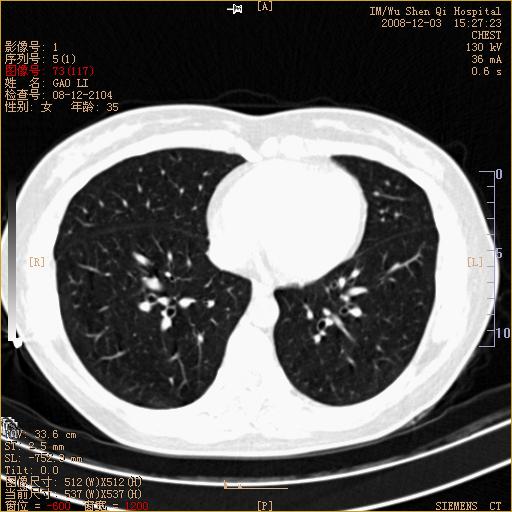

标题: CT16895:女,35岁,反复咳嗽数月,只传部分图像,是否考虑 [打印本页]

标题: CT16895:女,35岁,反复咳嗽数月,只传部分图像,是否考虑

左下肺支扩

典型“印戒征”。

印戒征,支持支扩.

左下肺扩支

不是十分典型。

未见明确异常。

印戒征,支扩